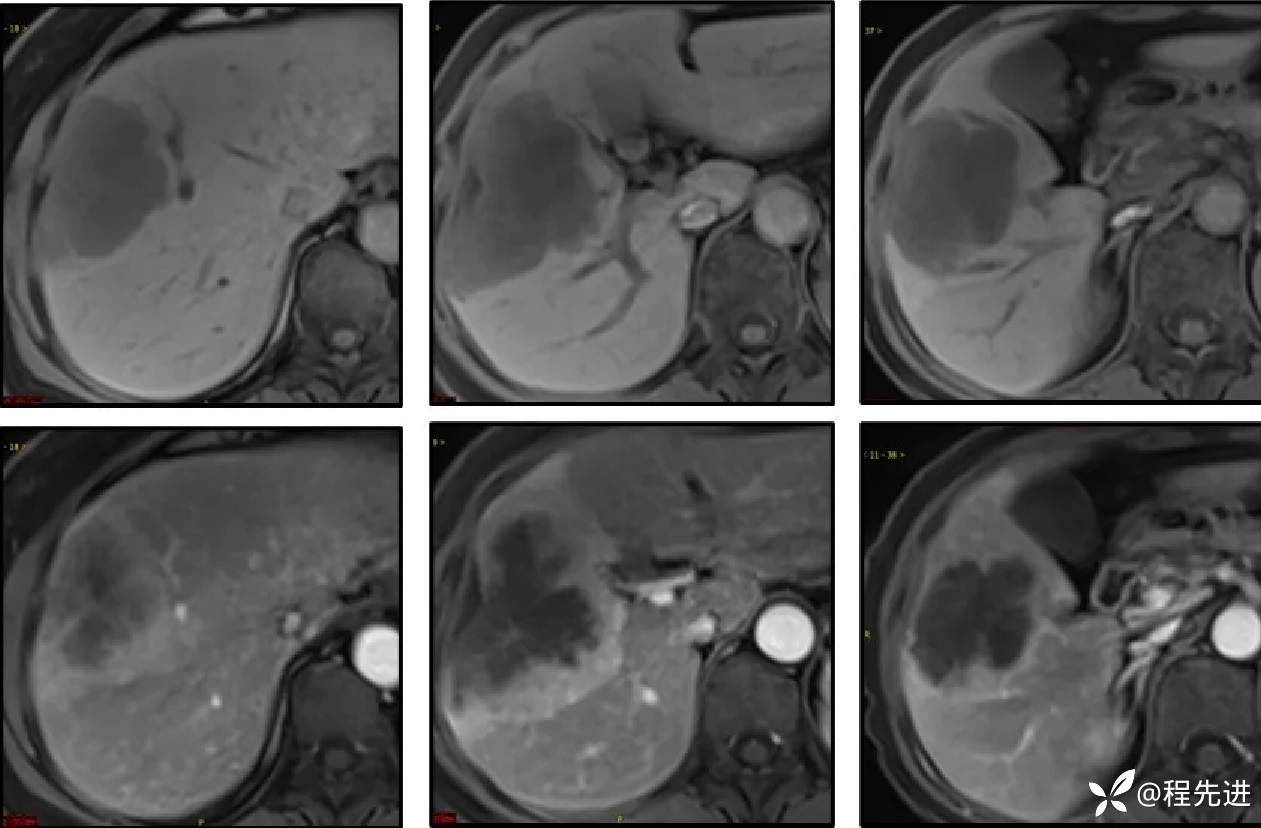

CT增强,3期:

平扫、动脉期:

静脉期、延迟期: